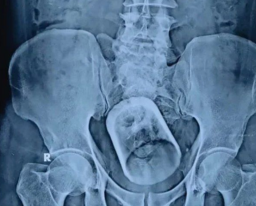

Ia menjelaskan, untuk memastikan penyebab dan penanganannya, dokter perlu mengevaluasi dengan melakukan pemeriksaan fisik yang komprehensif dan pemeriksaan penunjang seperti rontgen, MRI, dan CT Scan.

Ia menjelaskan beberapa penyakit degeneratif yang bisa terjadi di ruas tulang belakang adalah penyempitan rongga tulang belakang (stenosis spinal), hernia nukleus pulposus, osteoartritis, dan sendi facet yang menebal. Semua proses degeneratif pada tulang belakang itu dapat menyebabkan nyeri berkepanjangan yang juga disertai kebas, kesemutan hingga sulit menggerakkan kaki atau tangan. Sehingga selain keseleo, ada tiga penyebab nyeri tulang belakang lainnya adalah: